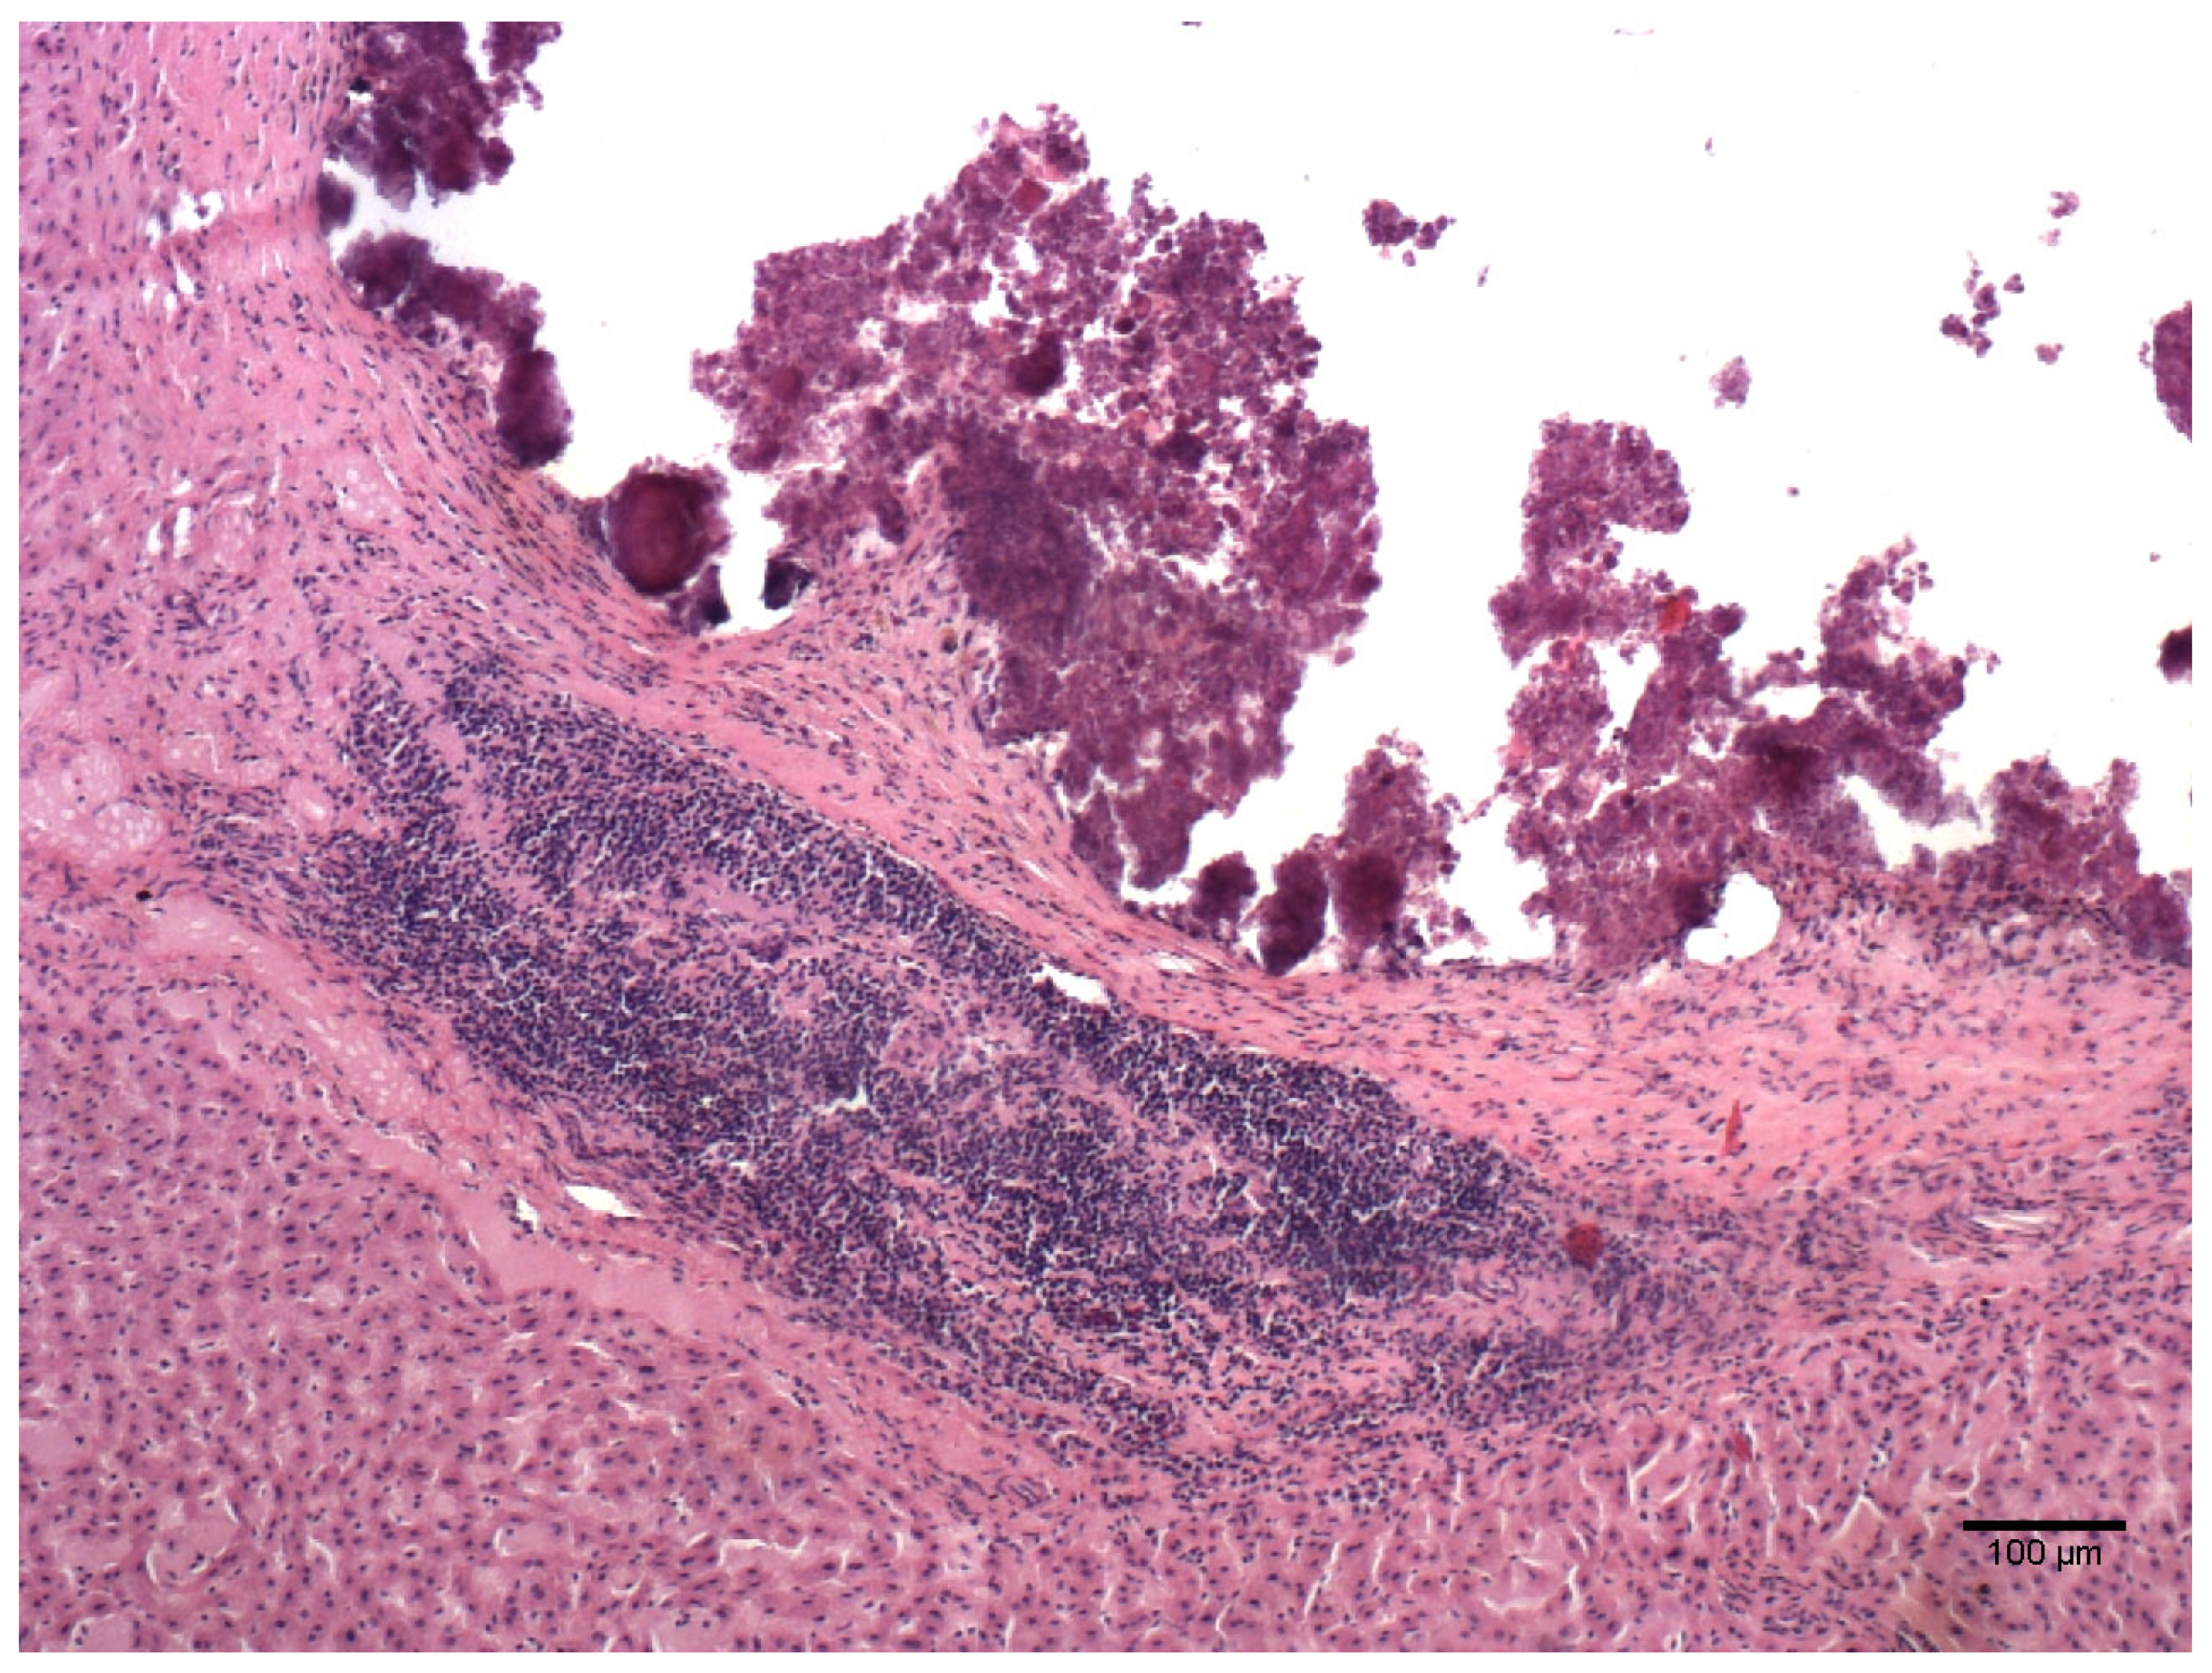

3.2. Histological Analysis

| Lesion | Number of Samples Positive for the Lesion/Total Number of Microscopical Lesions (%) |

|---|---|

| Emphysema | 44/44 (100%) |

| Oedema | 36/44 (81.8%) |

| Parenchymal lymphocytic infiltrate | 36/44 (81.8%) |

| Perivascular lymphocytic infiltrate | 32/44 (72.7%) |

| BALT activation | 27/44 (61.4%) |

| Alveolar thickening | 12/44 (27.3%) |

| Atelectasis | 9/44 (20.5%) |

| Parenchymal lymphocytic and eosinophilic infiltrate | 2/44 (4.5%) |

| Lymphocytic bronchitis | 2/44 (4.5%) |

| Parenchymal neutrophilic infiltrate | 1/44 (2.3%) |

| Focal haemorrhages | 1/44 (2.3%) |